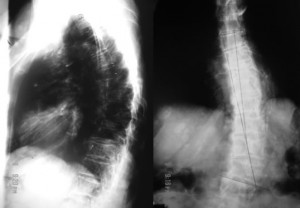

The radiographs are frontal and lateral views of her thoracic spine. They show:

1. Diffuse osteopenia.

2. Levoscoliosis of the mid and lower thoracic spine.

3. Compression fractures of the eighth and ninth thoracic vertebrae.

4. Numerous round well-defined soft-tissue masses attached to the chest wall.

The key to the radiologic diagnosis of this case lies in the non-calcified cutaneous masses of varying sizes. It is easy to assume the masses are within the patient’s thorax but a closer look shows that most are well-defined, have lucent halos around them and, so, are external to the chest wall. They are pathognomonic of von Recklinghausen’s disease (neurofibromatosis type1). The patient is osteoporotic and the vertebral compression fractures may be due to this.